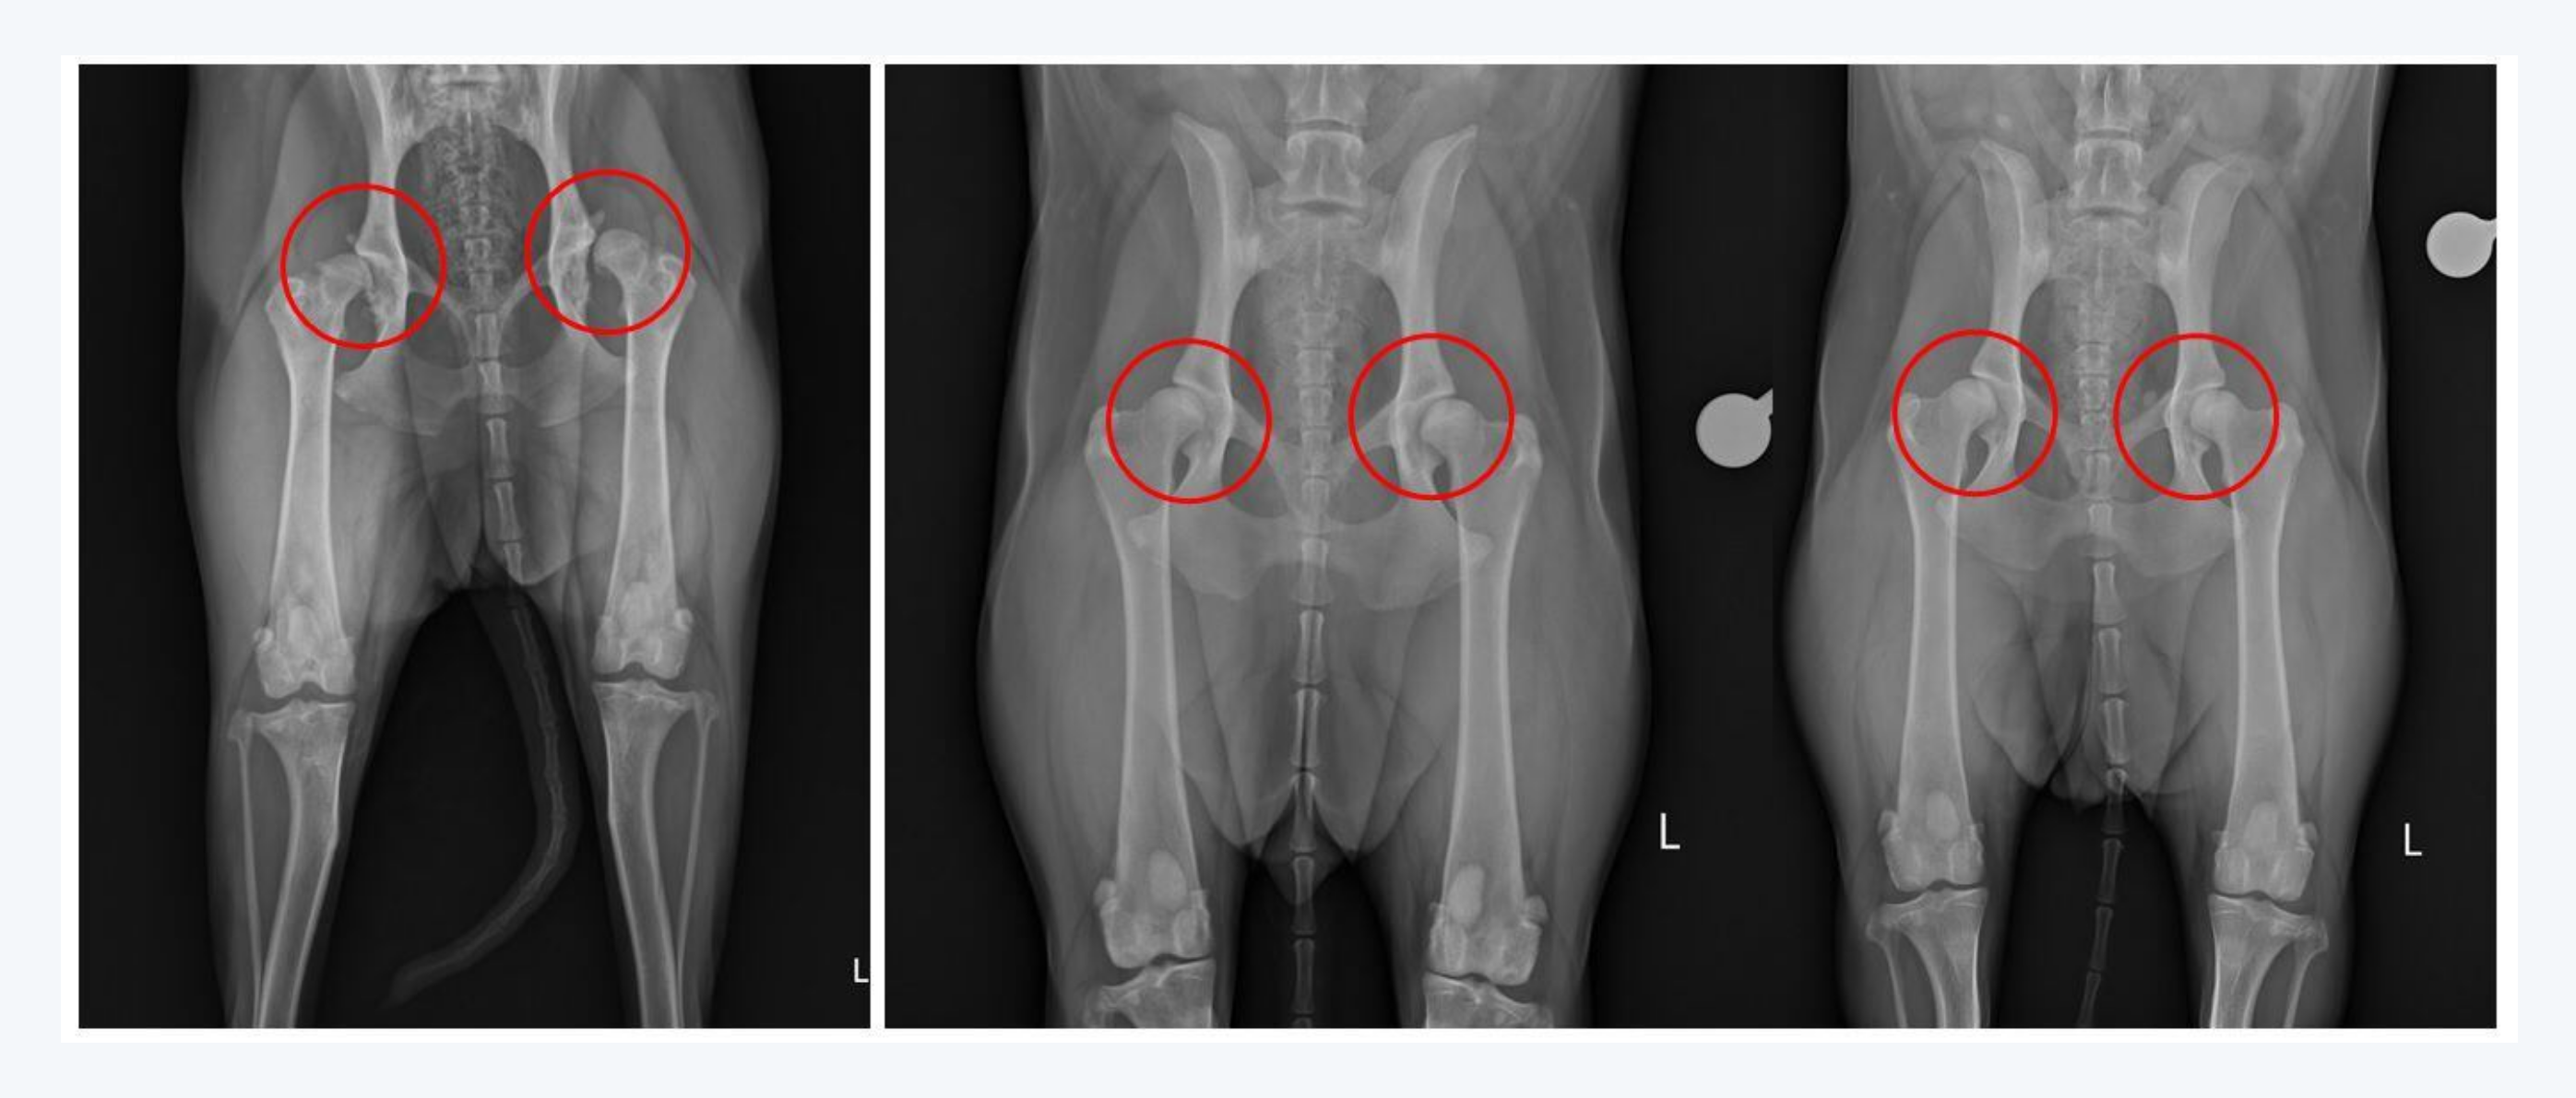

현재에는 과학의 발전과 함께 과거의 문제점을 바로잡기 위한 연구자와 관계자들의 부단한 노력이 이어지고 있습니다. 안내견으로 잘 알려진 래브라도 리트리버 품종도 앞선 불독과 같이 지속적인 근친교배로 인해 고관절 형성에 이상이 발생하여 통증과 움직임을 제한하는 고관절 이형성증으로 크게 고통받아왔습니다. 하지만 최근 국립 충남대학교 김민규 교수팀에서 고관절 이형성증을 유발하는 유전자 돌연변이를 교정한 래브라도 리트리버 복제 개를 생성에 성공하여 래브라도 품종에 씌어있는 "저주"의 연결고리를 끊어낼 수 있는 새로운 방향을 제시하였습니다. 우리나라의 대표적인 육우인 한우에서도 전국 200만 마리에 달하는 한우의 아버지 격인 종모우를 대상으로 지속적인 DNA 검사를 통해 유전병 보인자 유무를 선별하여 유전병의 발생을 최소화하고 있으며 교배 계획을 수립할 때 유전적인 유사도를 고려하여 근친교배를 지양하는 노력을 더 하고 있습니다. 호주 시드니대학교에서 운영하는 OMIA(Online Mendelian Inheritance in Animals)는 약 520여 종의 동물에서 확인되는 유전형질과 변이 및 유전병을 데이터베이스화하여 지속적으로 업데이트를 통해 유전병 연구에 이바지하고 있습니다.

래브라도의 고관절 (좌측)고관절 이형성증을 보이는 일반 래브라도의 고관절, (우측)정상적인 고관절을 보여주는 복제 래브라도 (출처: scientific reports)